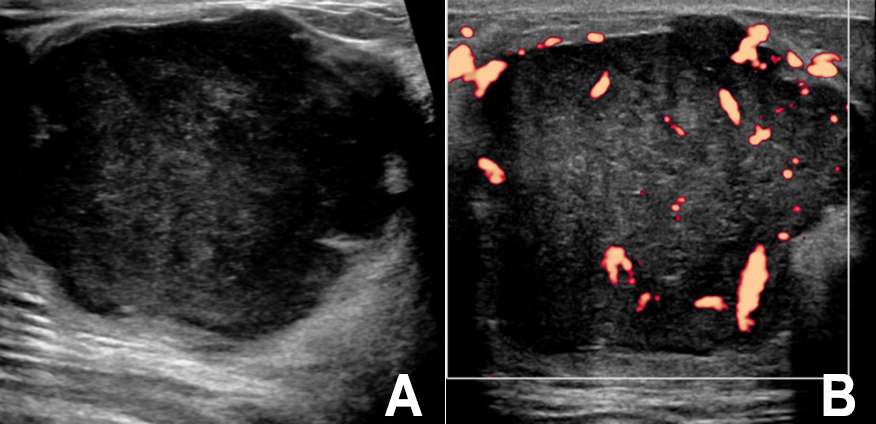

Case: Breast Sarcoma Figure 2

Figure 2: Targeted ultrasound of the palpable mass (biopsy proven spindle cell sarcoma, see Figure 1) demonstrates a large hypoechoic mass in the left breast at 2 o’clock, 1 cm from the nipple with lobulations measuring 4.8 x 4.1 x 4.9 cm (A). Doppler static image demonstrates internal vascularity (B).

As with mammography, the sonographic appearance of breast sarcoma is nonspecific. Breast sarcomas may be oval, hypoechoic or mixed echogenicity masses with microlobular or indistinct margins. They often demonstrate internal vascularity and posterior acoustic shadowing4 (Figure 2).